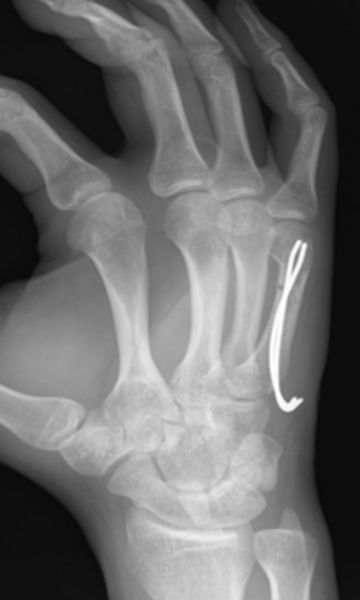

Die operative Versorgung der Metacarpale V Frakturen erfolgt entweder in der Regel mit Drähten, gelegentlich ist der Einsatz einer Plattenosteosynthese (Verplattung) notwendig.

Bei Metacarpale I Frakturen müssen Bennett – und Rolandofrakturen immer operativ versorgt werden, hier wird der Operateur entscheiden, ob eine Spickdrahtversorgung oder eine Plattenosteosynthese erfolgt.